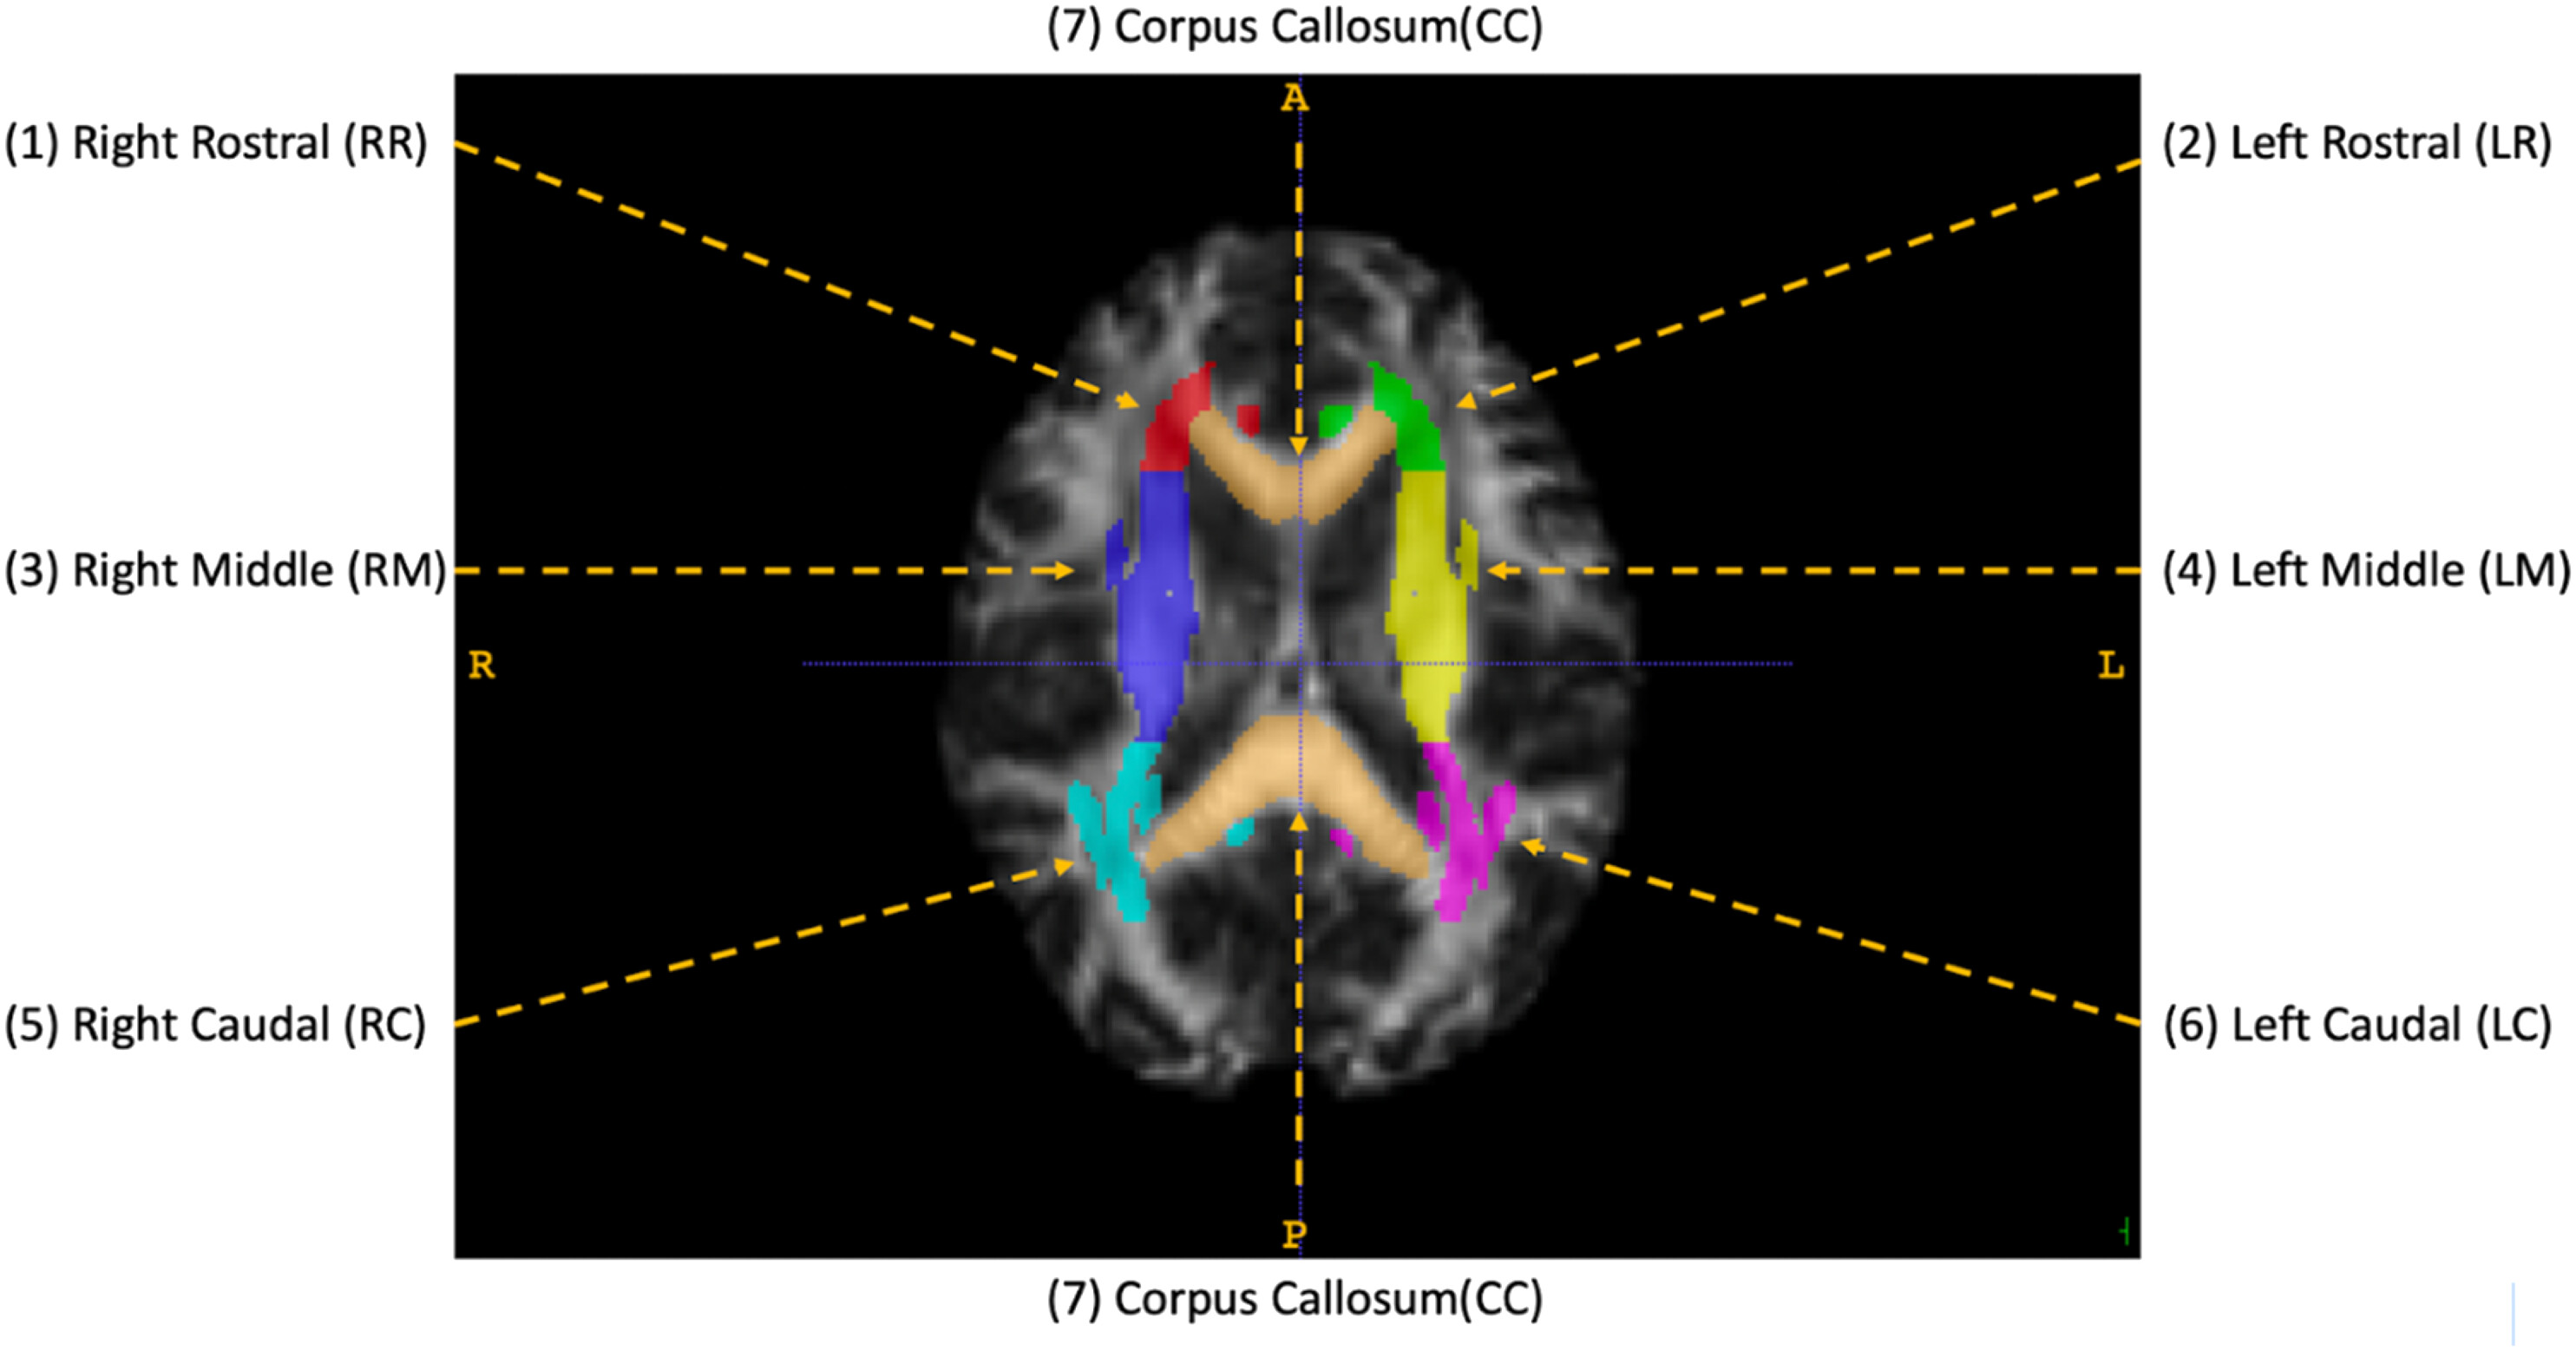

在调查中,研究人员分析了2016年至2018年期间拍摄的81名男性运动员的核磁共振成像扫描结果,这些运动员在此期间均未确诊脑震荡。接触性运动的运动员参加了橄榄球、长曲棍球和足球,而非接触性运动的运动员则参加了棒球、篮球、田径和越野赛。

研究小组训练该程序识别脑组织中的异常特征,并根据这些因素区分反复受到头部伤害的运动员和没有受到头部伤害的运动员。他们还对每个特征对检测损伤的有用程度进行了排名,以帮助发现在众多核磁共振成像指标中哪些指标可能对诊断最有帮助。

作者说,有两个指标能最准确地标记出头部损伤导致的结构变化。第一个指标是平均弥散度,用于测量水在脑组织中移动的难易程度,通常用于在核磁共振成像扫描中发现中风。第二种是峰度均值,它能检测脑组织结构的复杂性,并能显示大脑中与学习、记忆和情绪有关的部分发生的变化。